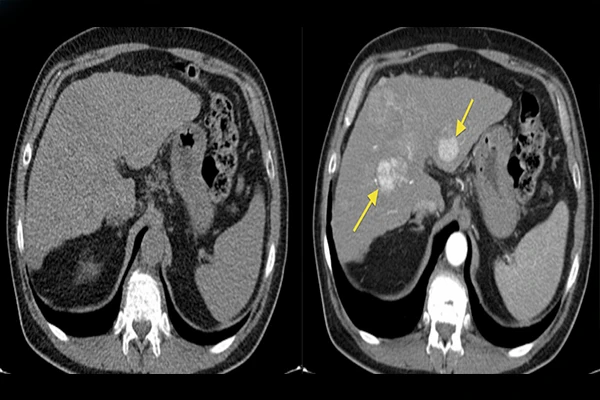

The Role of Contrast Agents in Radiology: A Practical Guide

Learn about iodine, gadolinium, and barium-based contrast agents, including their uses and safety.